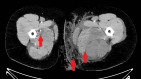

Figure 3. Axial post-contrast CT of the bilateral thighs

Axial contrast-enhanced CT shows left greater than right thigh muscle enlargement, muscle edema, and heterogeneous muscle enhancement, most pronounced in the bilateral adductor and posterior thigh compartment musculature. Marked inflammatory changes and edema are also demonstrated within the left medial thigh subcutaneous soft tissues. Arrows mark some of the heterogeneous enhancement and muscle edema in each extremity, as well as inflammatory changes in the subcutaneous tissue of the left thigh.